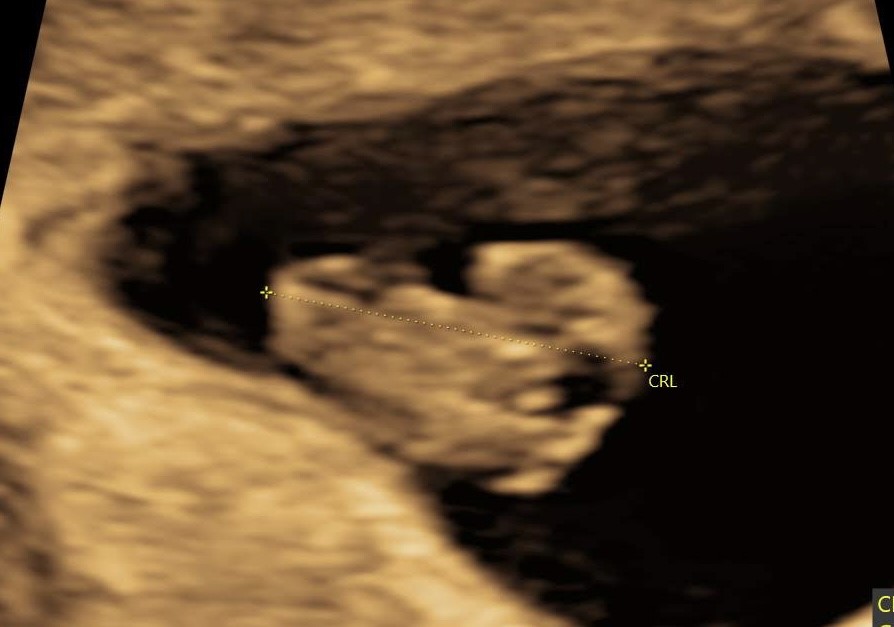

Her 8+2 med udvendig scanning.

Vedhæftede fotos (klik for at se i fuld størrelse)